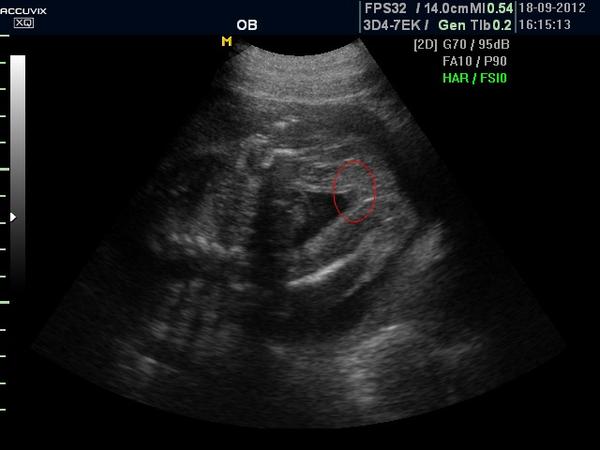

ty fotky co jsem sem dala jsou ze 13tt a to pohlaví vypadá tedy jako jsi sem @ronyx dala ..

A to je fakt nerozpoznatelný i když tady holky tipuji co vidí na mem snímku...... tak to mají muj obdiv

Ahoj holky.Dnes kontrola u dr. jsem 16 tt.Vyfotila mi rozkrok,ale já se v tom nevyzdám.Nevím ani kde jsou nohy natož kde má být údajně pohlaví.Je tu nějaký odborník který to pozná? 🙂 Dr. mě napíná a prý nechá na jiném dr. ať mi řekne co to bude.Kontrola ale až za měsíc 😒

@jarmulka Nevyznáš se v tom prosím ty? 😒 Obě fotky jsou stejné,jen ta druhá je zvětšenina

A můžete mi prosím holky některá z vás nějak zakroužkovat,kde mám hledat?Já fakt ani nemám ponětí 😀

Holky,kde tam vidite pindoura s kulkama?ja se tady snazim stahnout aplikaci do telefonu,abych mohla fotku oznacit a furt nemuzu nic najit ☹ chtela bych oznacit to kavove zrno,ktere vidim 😀

@anetka1701 no tak tam presne vidim kavove zrno 😀

@emily2015 kávová zrna jsem viděla zatím naživo dvě a nějak to vypadalo prostě jinak než tohle... :oD

@anetka1701 ja jsem zase videla na utz pytlik s kulkama a take to vypada naprosto jinak 😀